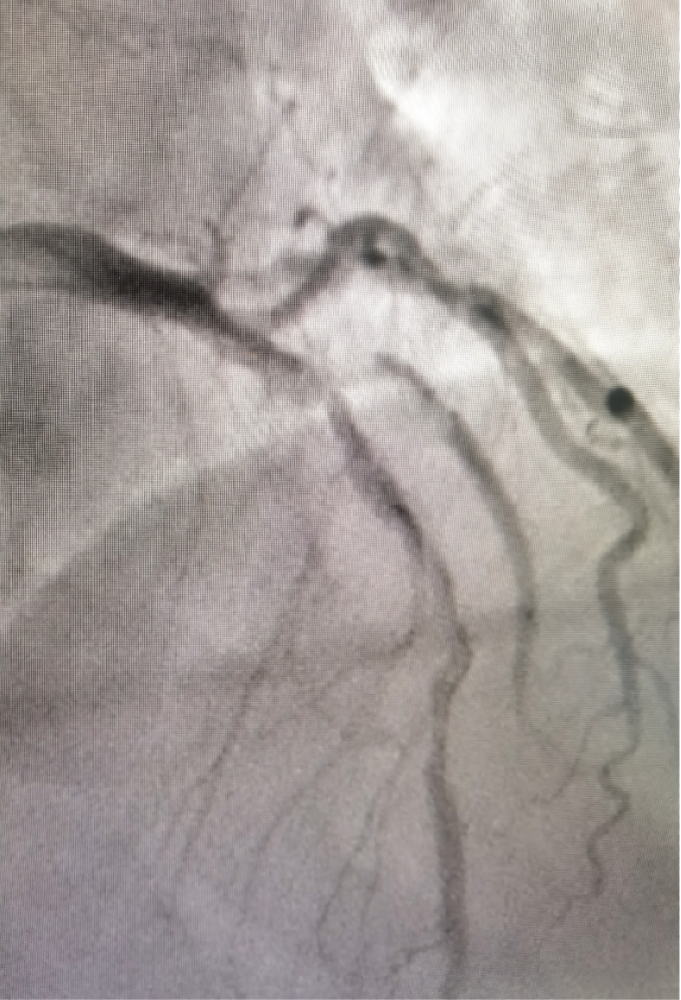

造影结果示:前降支分叉病变,90%狭窄,对角支90%狭窄伴血栓影。田灵萍主任介入团队认真分析病变特点后,拟予对角支药物球囊扩张+前降支支架植入。给予血栓抽吸、球囊反复扩张后,对角支仍有80%狭窄,药物球囊扩张方案被迫排除。

田灵萍主任认真分析患者冠脉病变特点后,果断决定行双支架植入术,采用Culotte术式。经过90分钟的努力,手术顺利完成,患者转危为安。

18日下午,一位急性广泛前壁心肌梗死患者,造影结果如出一辙,只是血管的直径、分叉病变的角度略有不同。分析患者冠脉病变特点,田灵萍主任决定采用DK Crush术式。最终,经过我科大夫严谨制定手术策略,认真每一步操作,手术再次顺利完美结束。